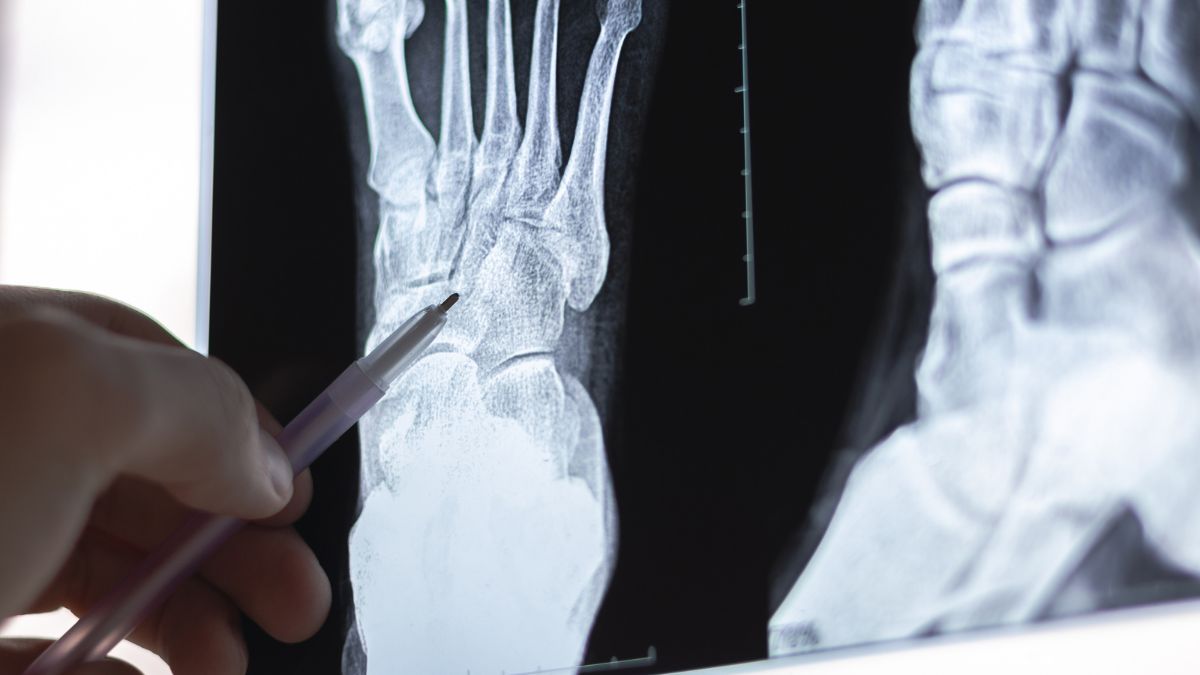

HPP niemowlęcą rozpoznaje się w ciągu pierwszych sześciu miesięcy życia. Na zdjęciach radiologicznych widoczne są charakterystyczne zmiany krzywicze i często występują złamania. Niemowlęta nie rosną prawidłowo, a niektóre doświadczają drgawek reagujących na witaminę B6. Często występuje hiperkalcemia i nefrokalcynoza. Objawy obejmują również problemy rozwojowe. Ważne jest, aby otrzymać wcześnie właściwą diagnozę. Aby zdiagnozować niemowlę, konieczne może być wykonanie zdjęcia rentgenowskiego całego ciała. Podobnie jak w przypadku postaci okołoporodowej, zachorowalność i śmiertelność są zmniejszone dzięki leczeniu asfotazą alfa.

Wiemy jednak, że im niższy poziom fosfatazy zasadowej, tym cięższy przebieg choroby. W przypadku perinatalnej formy hipofosfatazji pomocne w rozpoznaniu są także badania ultrasonograficzne. Obrazowanie radiologiczne (RTG) może z kolei potwierdzić obecność patologicznych złamań.

W 2015 roku w Unii Europejskiej zatwierdzono lek przeznaczony do długotrwałego leczenia pacjentów, u których choroba ujawniła się w dzieciństwie. Substancją czynną tego preparatu jest asfotaza alfa – enzym będący odpowiednikiem fosfatazy alkalicznej (ALP), której aktywność u chorych jest obniżona lub całkowicie nieobecna. W trakcie badań klinicznych z udziałem dzieci zaobserwowano poprawę stanu stawów na zdjęciach RTG oraz zwiększenie tempa wzrostu u większości uczestników.